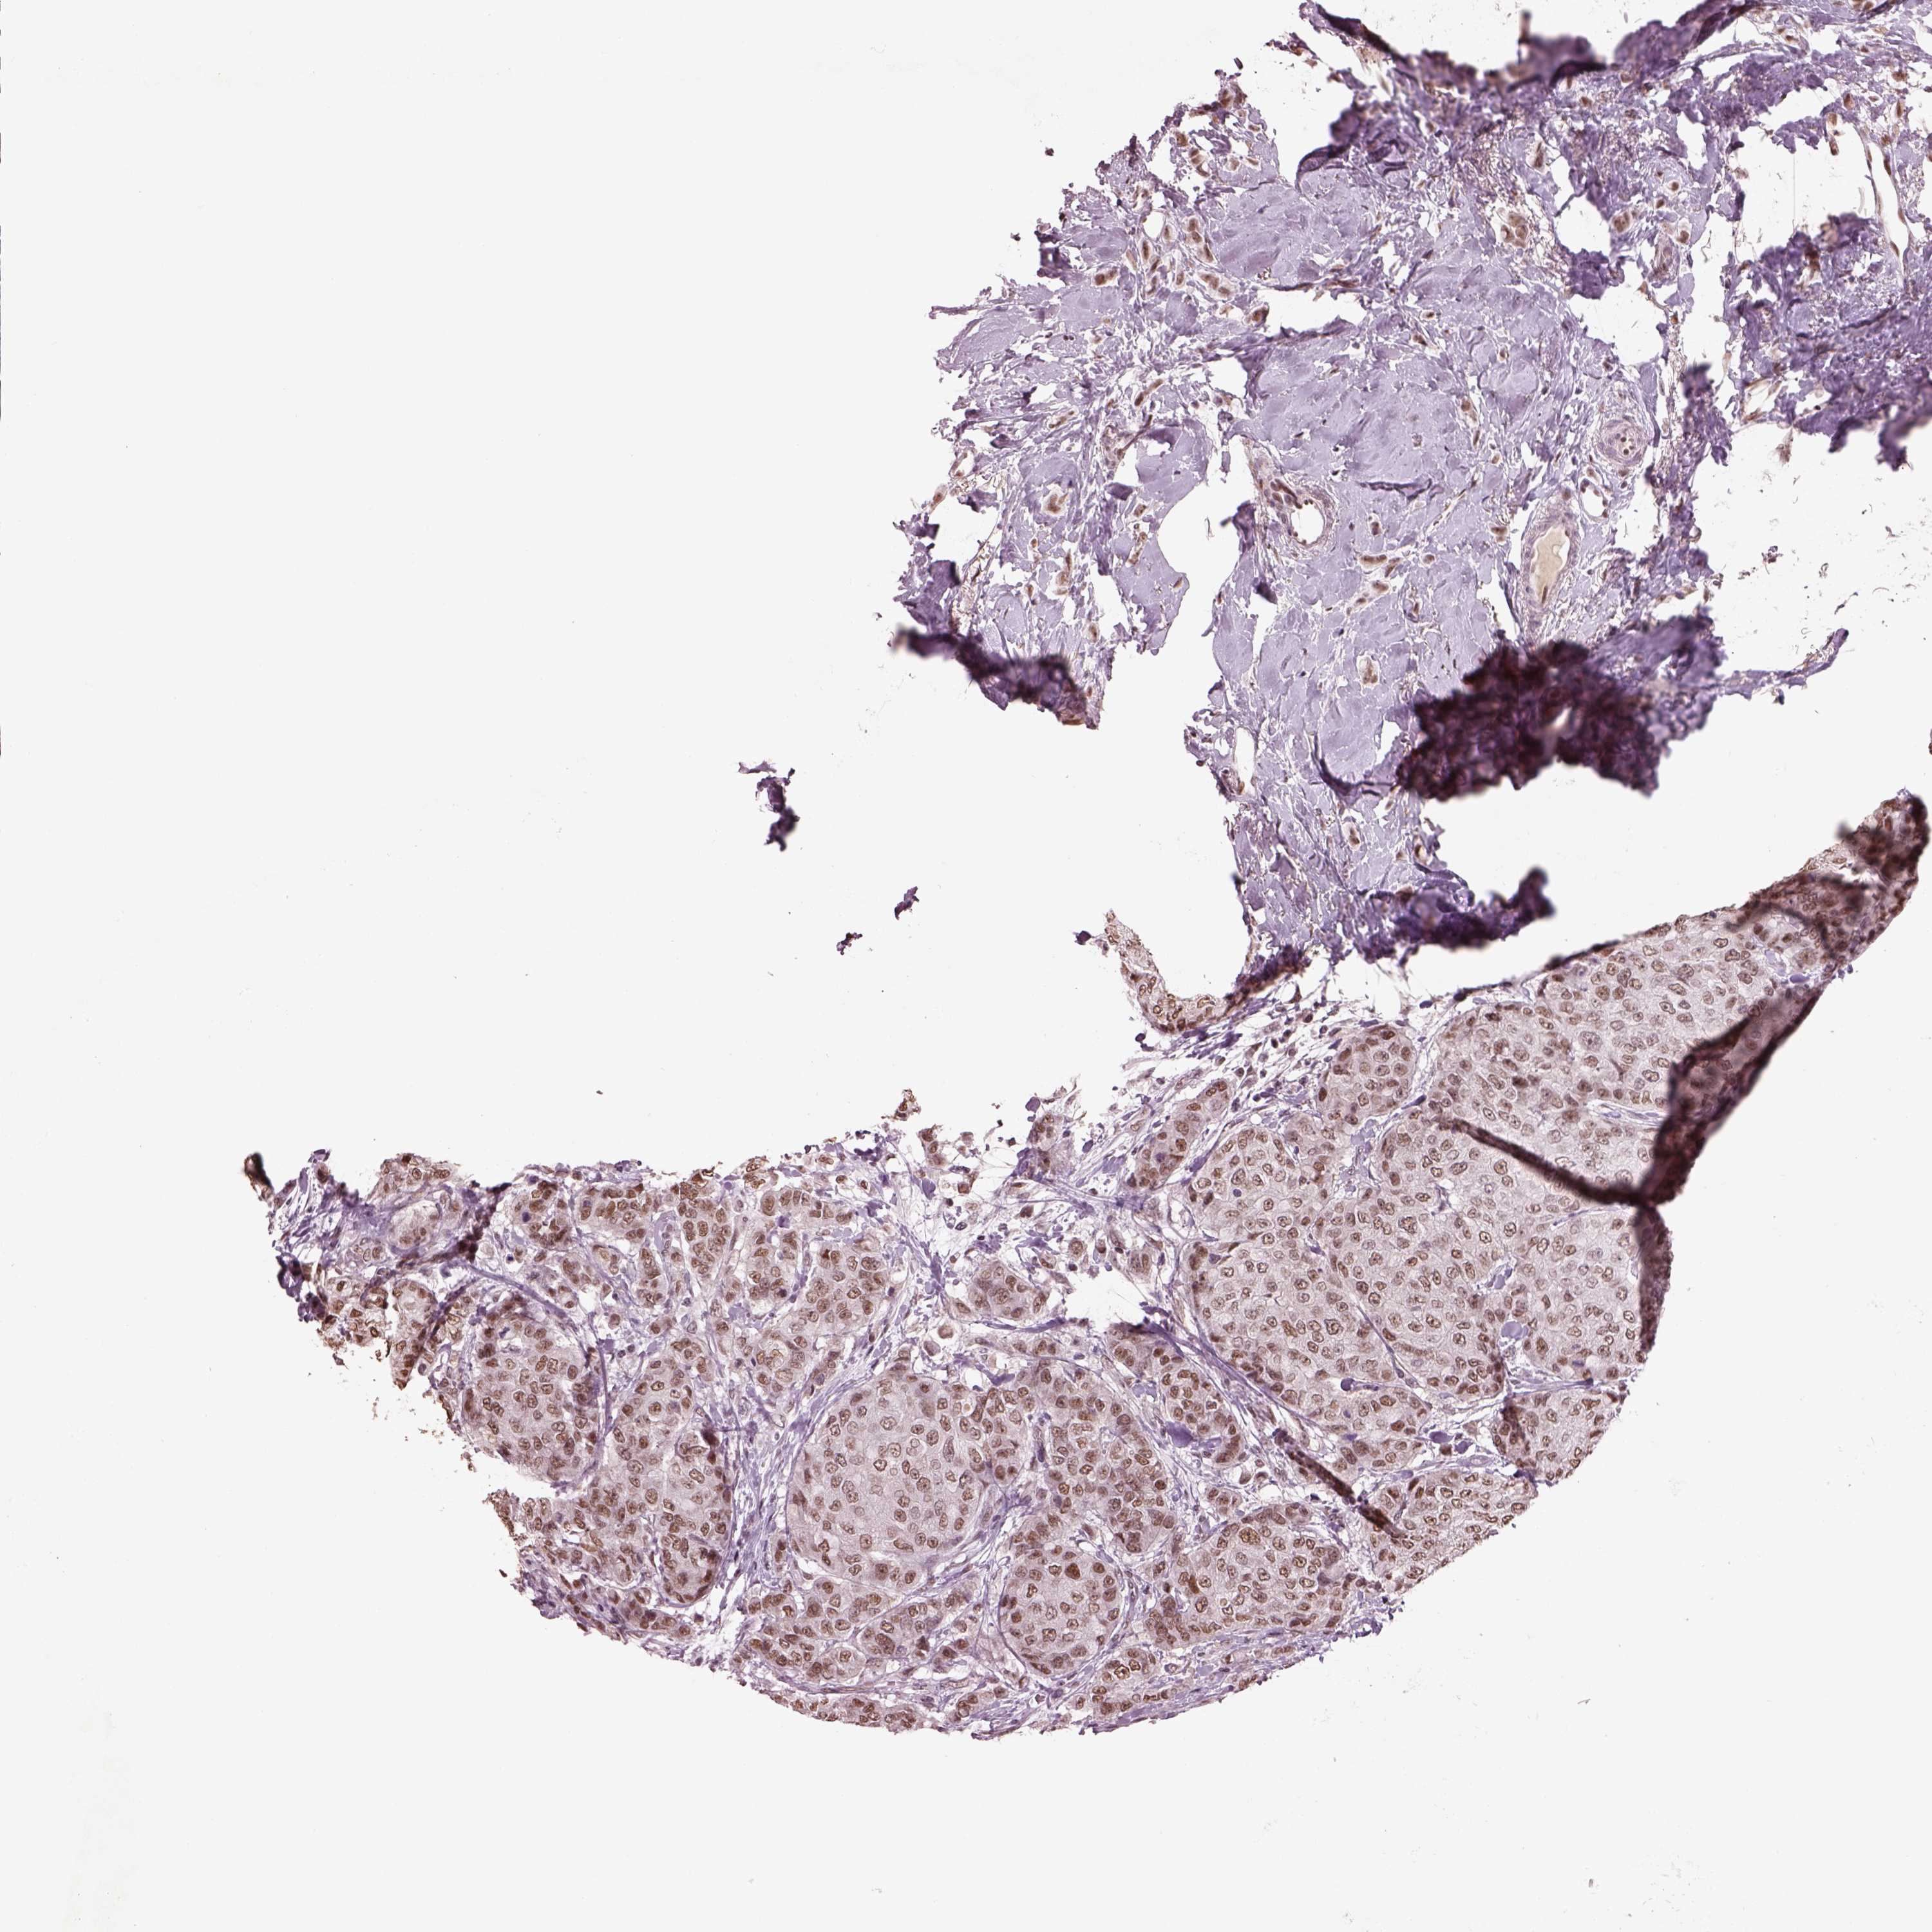

BRCA TCGA BRCA VALIDATION PROTEIN EXPRESSION

ANTIBODIES

AND

VALIDATION